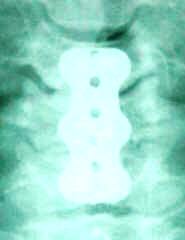

MRI done

2004 showed extruded disc C5-6 with right

foraminal occlusion. |

The patient was sent

for investigations and MRI of the lumbar spine

was uneventful, but there is huge central

extruded disc C6-7 more to the right compressing

the spinal cord with old extruded disc C5-6. |

Discectomy of C6-7 was performed and removal of

the all the extruded fragments compressing the

spinal cord was achieved. Intradiscal cleaning

of C5-6 was performed. Adequate Fidji cages were

inserted to both levels with Novabone. Using

Trinica Zimmer cervical plate 36 mm length 2

levels, fusion of C5-6-7 was done with screws 14

mm length. The construct was applied after

removal of all the projecting anteriorly

osteophytes. The gaps between the cages and

anterior edges of the bones was filled by his

own bone harvested from the ossified annulus

fibrosis. |